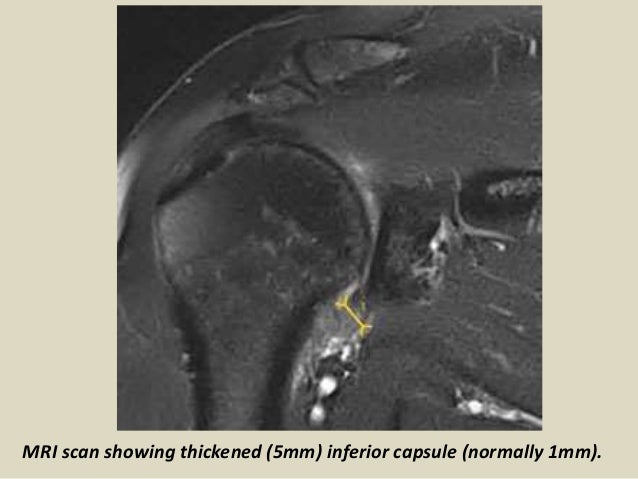

Как лечат адгезивный капсулит

Как лечат адгезивный капсулит 112 фото